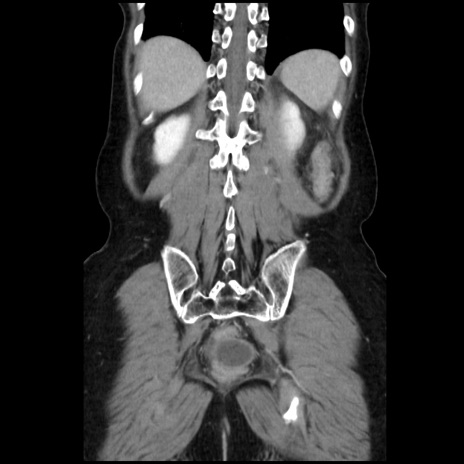

症例32(冠状断像)

【症例】40歳代 女性

【主訴】上腹部痛、嘔気・嘔吐

【現病歴】約9時間前頃から急に上腹部痛、嘔気、嘔吐が出現。改善しないため救急要請。

【既往歴】子宮頚癌(広汎子宮全摘術、放射線療法)、腸閉塞

【身体所見】腹部:平坦、軟、腸雑音亢進、上腹部を中心に腹部全体に圧痛あり。

【データ】WBC 8400、CRP 0.03